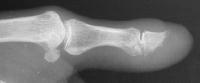

Comparison views of the opposite side:

Click for larger image